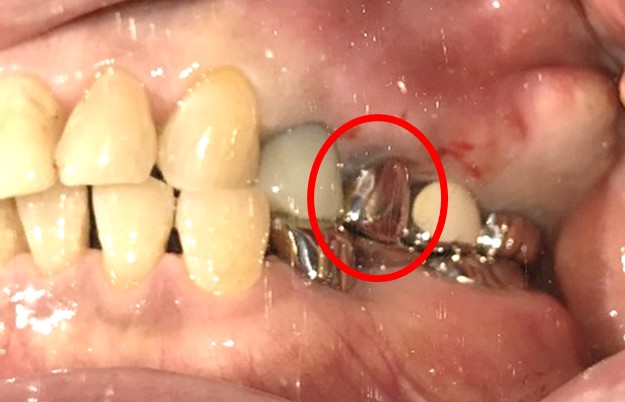

ブリッジの支台になっている奥の歯が、被せ物の中で虫歯になり、支台の役割を果たさず、前方の歯のみで支えられていました。前方の歯をそのままにして、後方の部分を切り離すと、そのまま取れてきました。中は、虫歯で歯根しか残っていない状況でした。この歯は、根管治療後、単独でオールセラミック冠を被せ、歯のないところにインプラントを埋入しました。

【インプラント埋入前】

冠はブリッジを切断しただけで取れてきました。軟化象牙質を取り除いたところ、歯根しか残っていない状況で保存できるかどうかのぎりぎりのところでした。